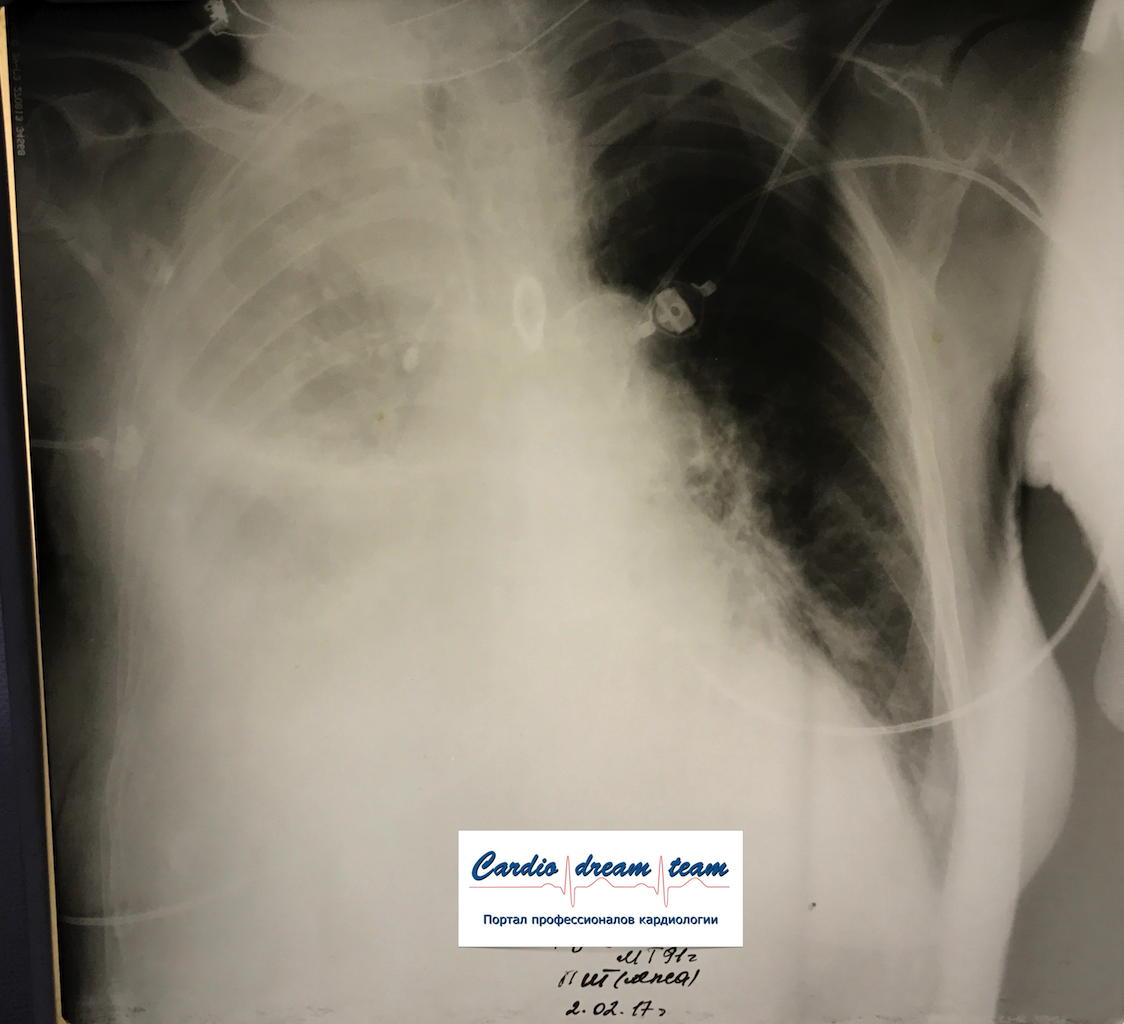

Гидроторакс. До и после пункции и лечения диуретиками.

Обсуждалось в Госпитале Ослабленных Сердец